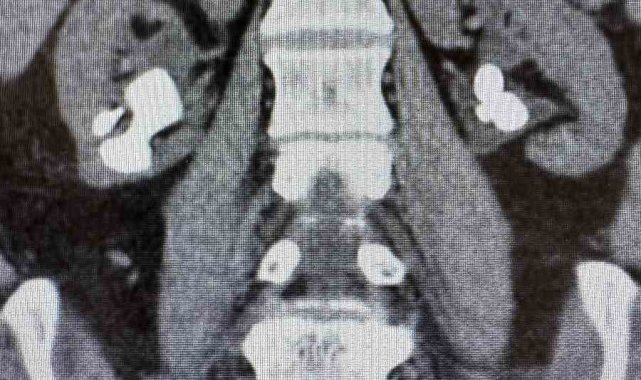

Üroloji Uzmanı Op. Dr. İlker Fatih Şahiner ve ekibince kapalı yöntemle (PNL) yapılan ameliyatlarda hastanın her iki böbreğindeki tekrarlayan sistin taşları temizlendi. Hastanın daha önce 10'un üzerinde böbrek taşı ameliyatı geçirdiği öğrenildi. Mayıs ayında yapılan ilk operasyonla sol böbrekteki taşlar alınırken, geçtiğimiz salı günü gerçekleştirilen ikinci operasyonla sağ böbrekteki taşlar da temizlendi.

Operasyonları gerçekleştiren Üroloji Uzmanı Op. Dr. İlker Fatih Şahiner, "Hastamızın her iki böbreğinde de tekrarlayan sistin taşları mevcuttu. Mayıs ayında sol böbreğine PNL yaparak taşsızlık sağlamıştık. Dün de sağ böbreğine PNL ameliyatını yaparak taşsızlık sağladık. Hastamızın genel durumu iyi, tedavisi servisimizde devam ediyor" dedi.